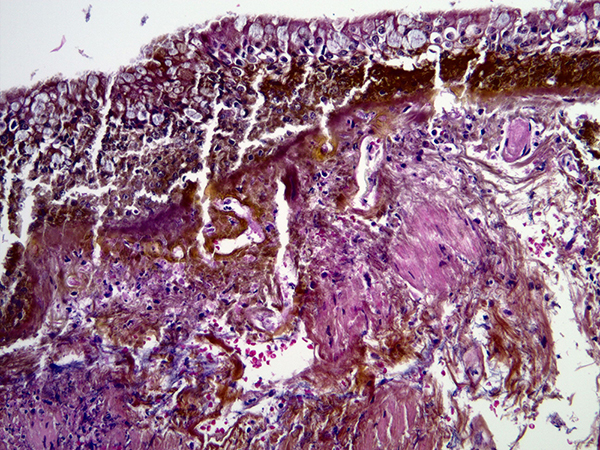

The most critical factor in making this diagnosis is an endobronchial biopsy, in which iron pill particles can be easily seen within bronchial mucosa (Figures 2 and 3), provided that the pathologist is aware of the morphology of iron pill particles on H&E. These particles can also be seen in bronchial brushing samples by cytopathologists. Iron pill (FeSO4) particles are elongated, fibrillary or crystalline, yellow to brown particles that are much larger in size than hemosiderin particles. They also differ in shape. Although both iron pill particles and hemosiderin stain strongly with a Perls’ stain (Figure 4), iron pill particles are usually extracellular whereas hemosiderin is typically found within macrophages. The appearance of iron particles in bronchial mucosal biopsies is identical to their appearance in biopsies from the gastrointestinal tract. The types of damage in the bronchial mucosa are also similar to the gastrointestinal tract, mucosal erosion and ulceration being common. Some patients develop bronchial stenosis in the long run.